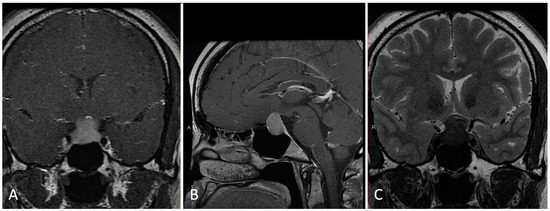

3.1. Sellar/Suprasellar

3.1.2. Illustrative Case

- An understanding of the osseous anatomy of the nasal corridor, paranasal sinuses, septum, intersinus septations, and relevant vascular structures are of paramount importance in the approach to sellar lesions.

- A pedicled nasoseptal rescue flap may be useful to obtain during the approach to the sellar lesions, particularly in cases of possible CSF leak, and should take into account the horizontal orientation of the posterior septal branch of the sphenopalatine artery.

- Dural opening of Rathke’s cleft cysts, one should begin anteriorly and inferiorly to minimize the risk of inadvertent CSF leak and iatrogenic injury to the pituitary gland.

- One must be mindful of diaphragm downward migration and identification during cyst resection to avoid a CSF leak.